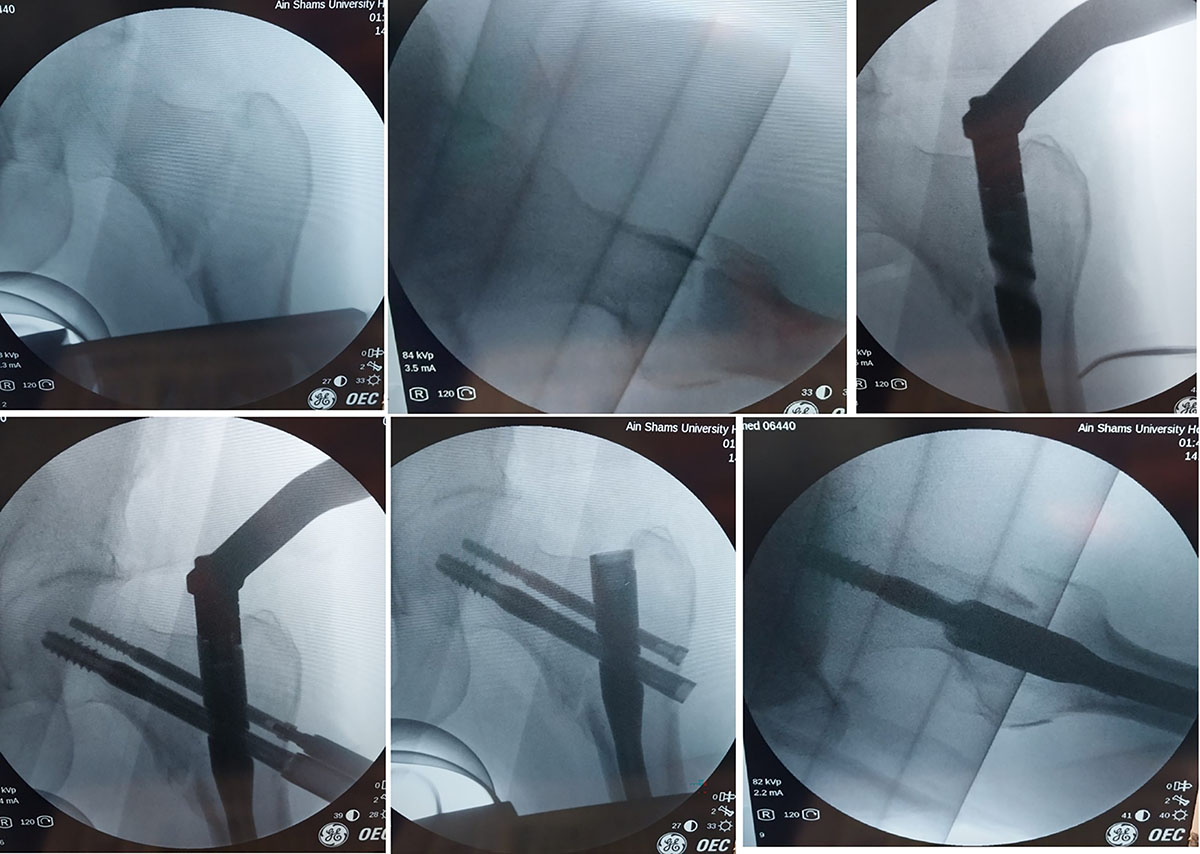

Fluoroscopic images of closed reduction and nail insertion in a patient of the supine position group.